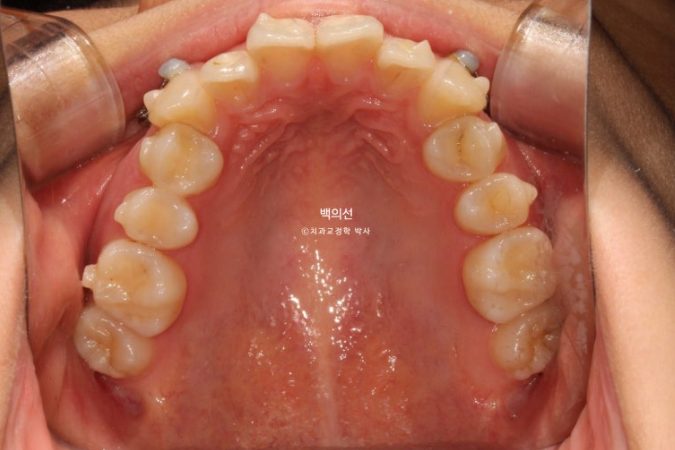

25.01

위에는 교정용 나사를 두 개 심어 송곳니 덧니를 가지런히 할 공간을 어금니 후방이동으로 얻기로 합니다.

클리피씨 장치를 붙인 사진이 없어 엑스레이로 대체합니다.

그렇게 클리피씨 장치를 붙인지 11개월째, 치료를 마무리 하였습니다.

25.07

교합은 좌우 정 1급을 달성했으며 좋습니다.